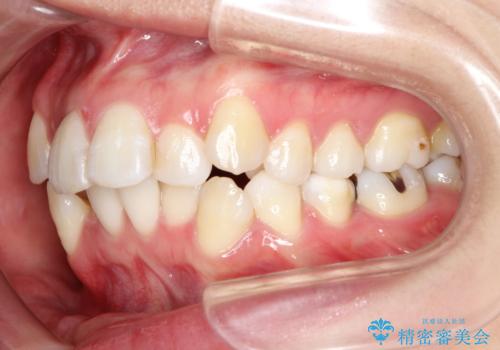

- 前歯のデコボコと上顎の前突感による口の閉じにくさを気にして来院された患者様です。

目立たない装置を希望されたので、上顎が裏側装置のハーフリンガルを選択し、上下左右の小臼歯(計4歯)を抜歯して矯正治療を行うこととしました。